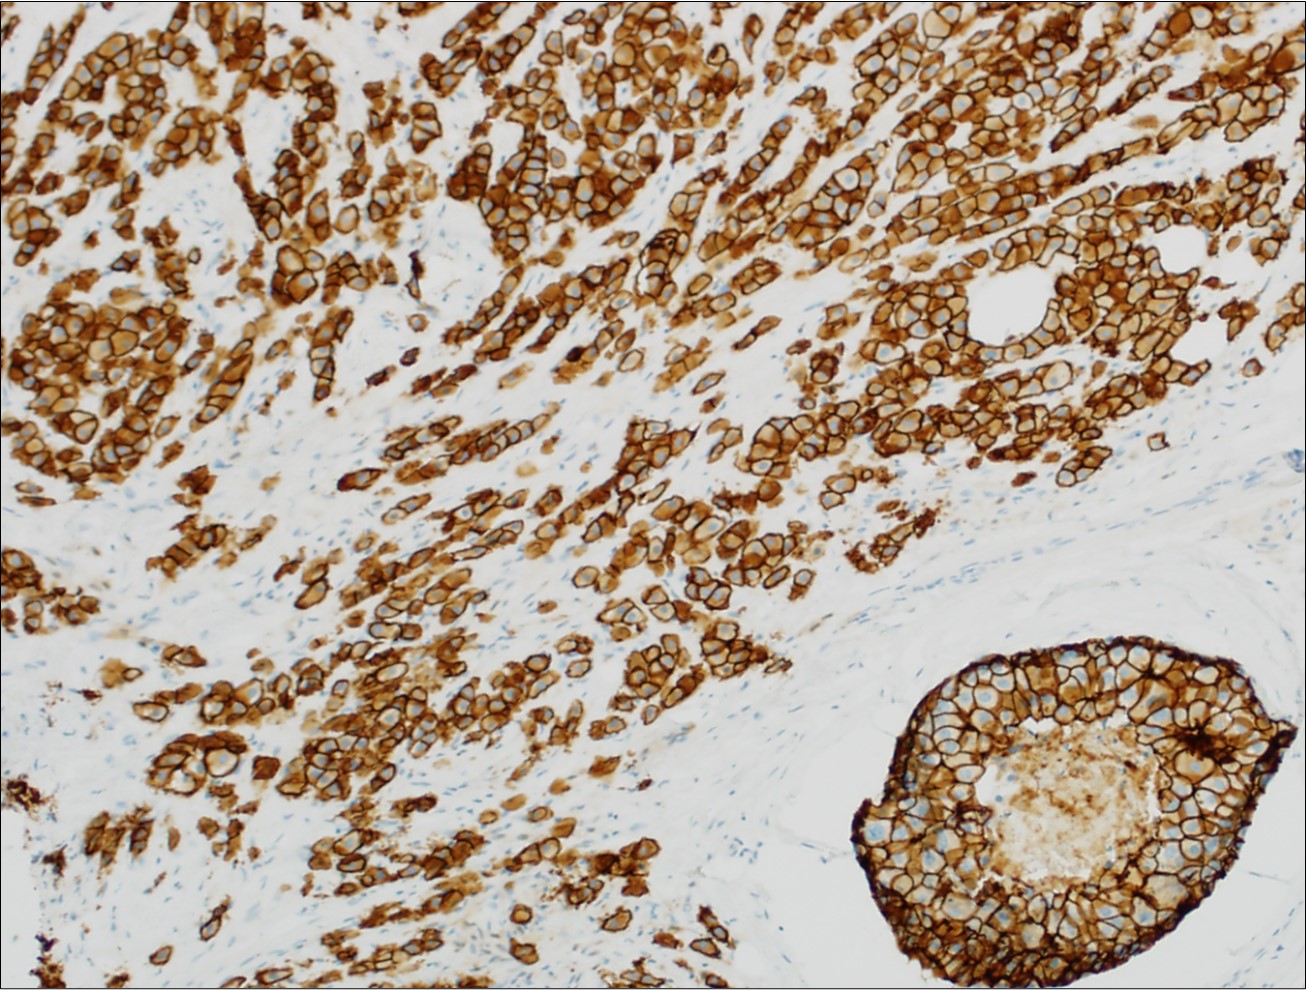

Microscopic (histologic) images

Contributed by Julie M. Jorns, M.D., Kristen E. Muller, D.O., Gary Tozbikian, M.D. and Emad Rakha, M.D.

Positive stains

- Luminal low molecular weight cytokeratins (CK8 / 18, CK19 and CK7 and pancytokeratins such as AE1 / AE3, CAM 5.2, MNF-116), EMA, E-cadherin, p120, ER (60 - 80%), PR (50 - 70%), HER2 (15 - 20%) (Am J Clin Pathol 2006;125:377)